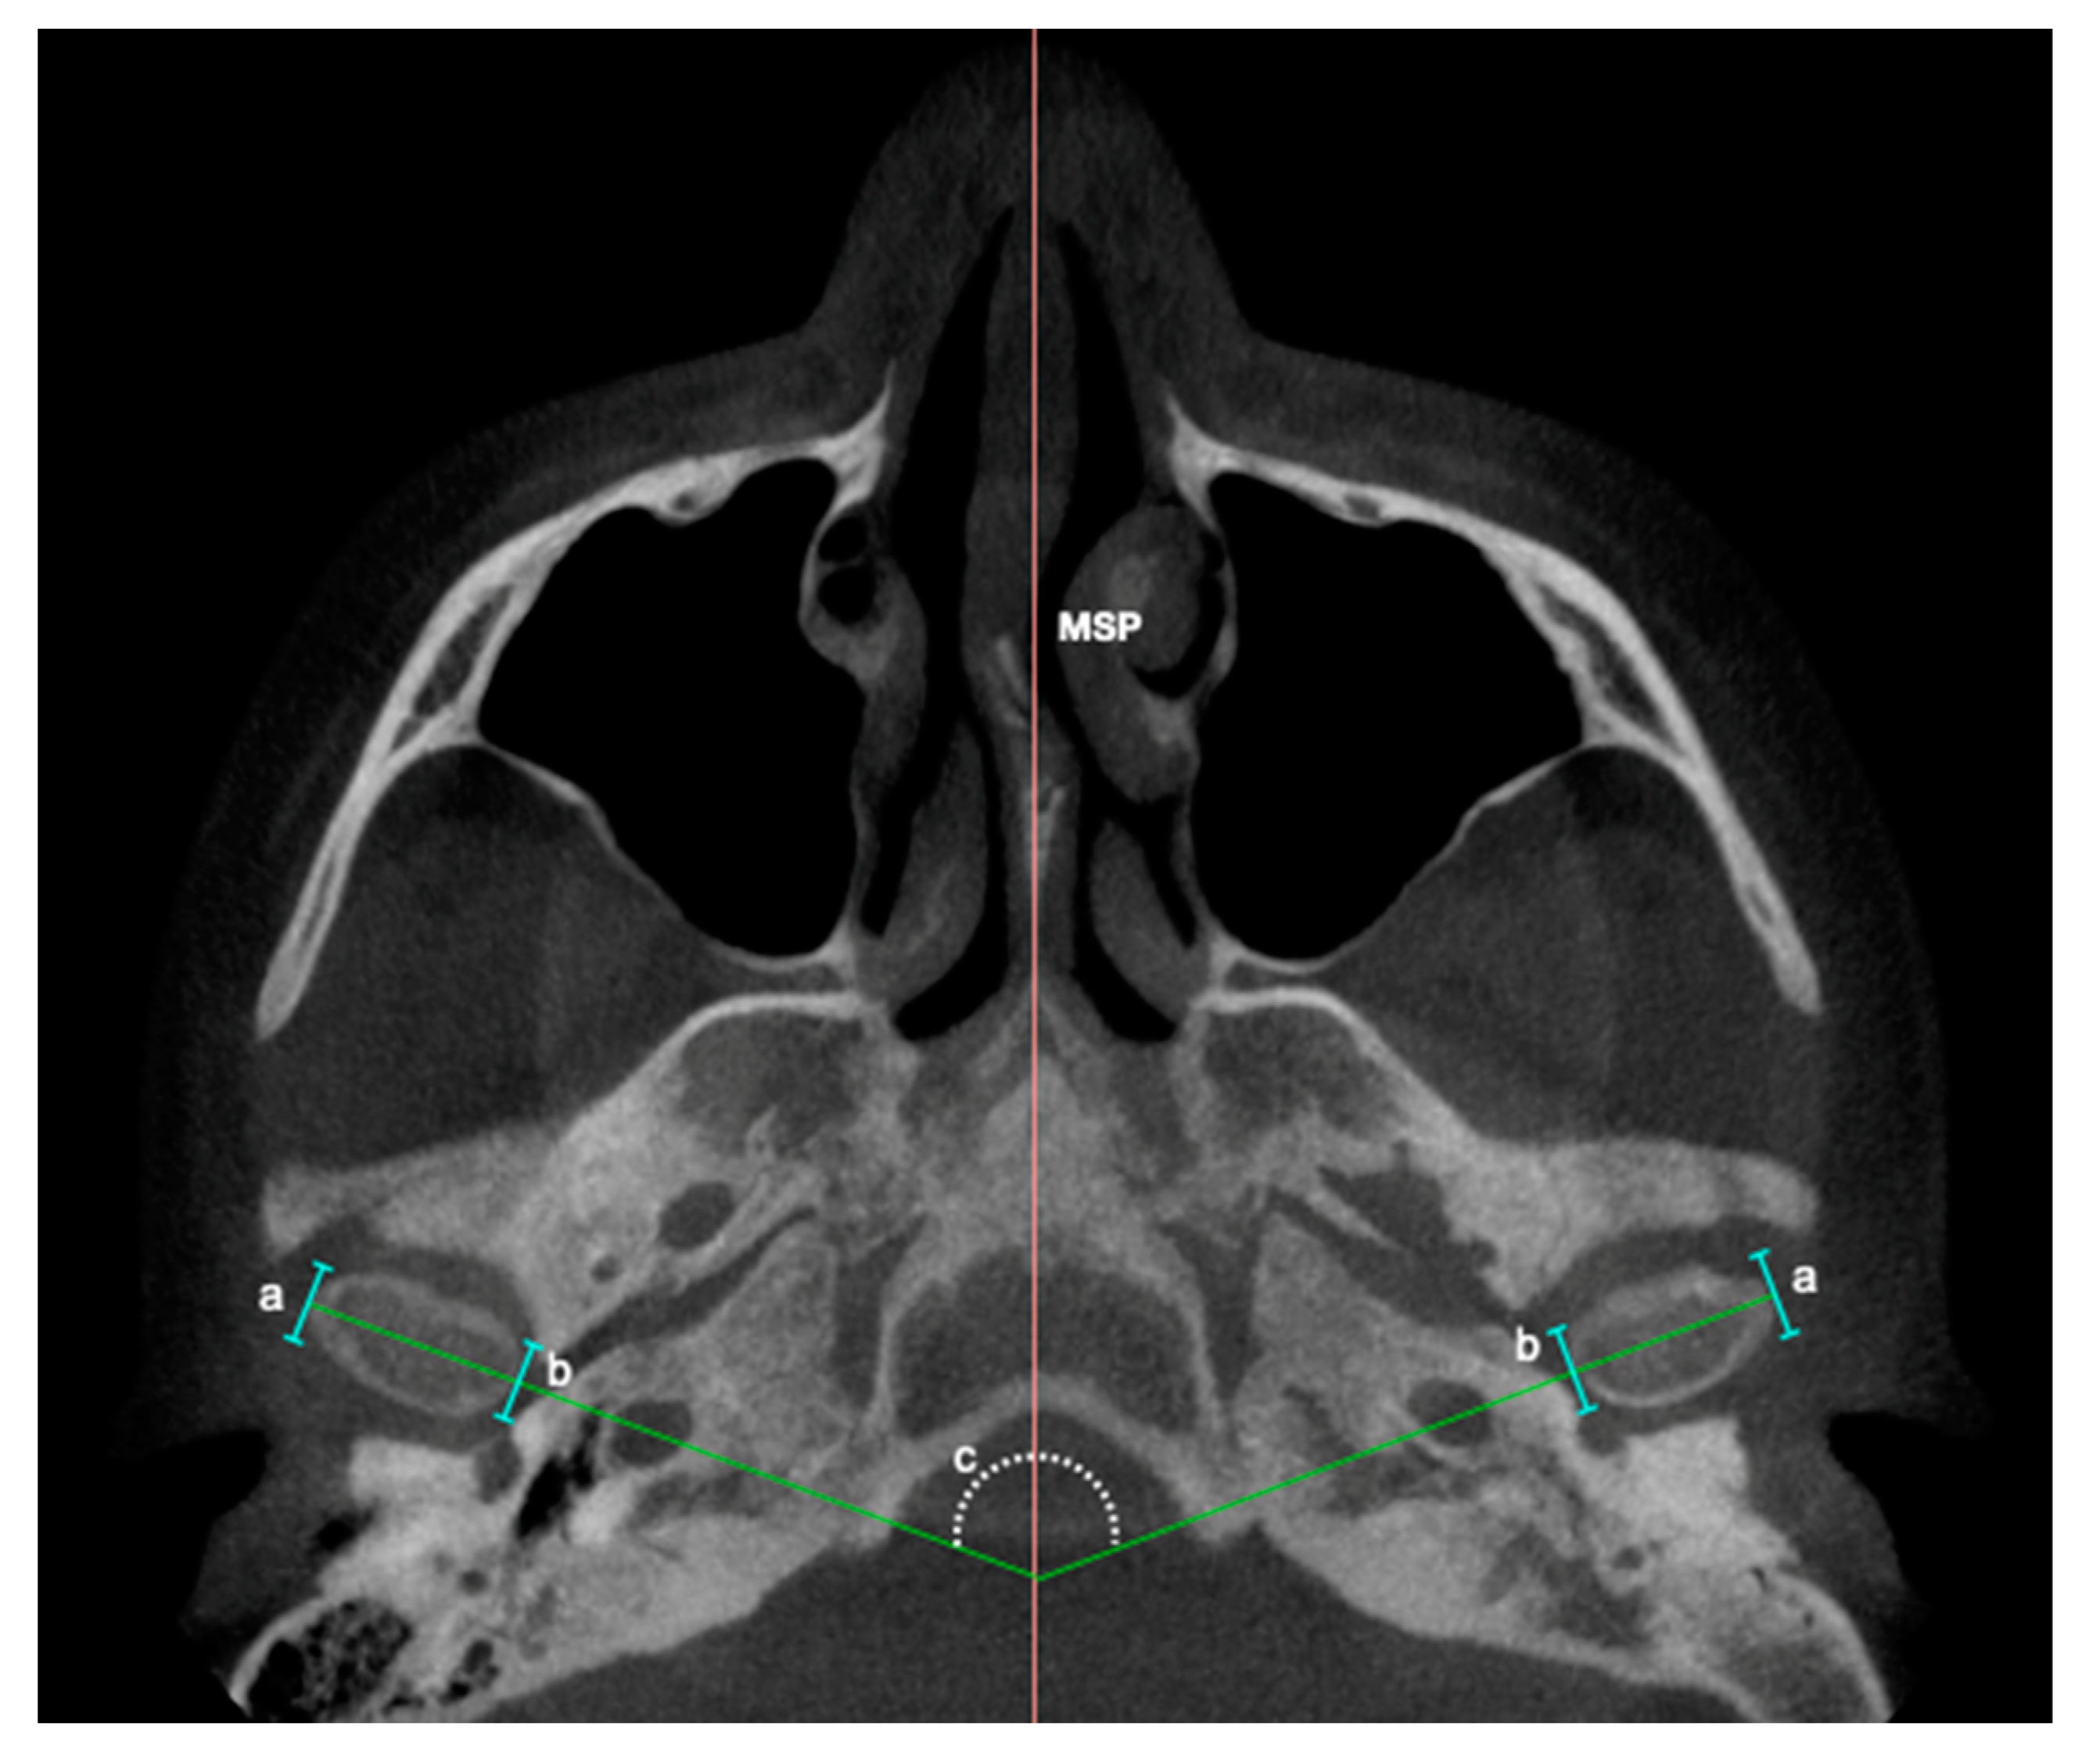

| Condylar axis | Inner angle between sagittal middle plane (SMP) and the line drawn from a projection of the highest middle-lateral length of each mandibular condyle. Figure 4. |